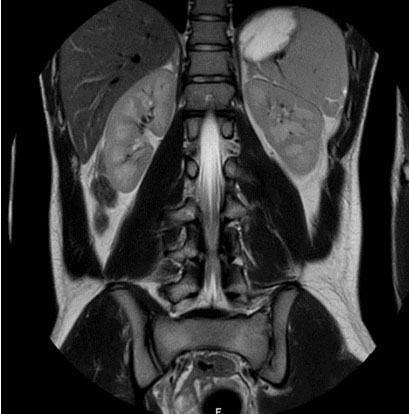

Computed tomography (CT) and magnetic resonance (MR) images of the adrenal glands demonstrated normal adrenal glands (Figure 4). There were no urinary tract malformations in imaging.

Figure 4: Adrenal glands on MR Imaging. Magnetic resonance coronal T2-weighted image demonstrating normal adrenal glands.

The hallmark of the SV-CAH is virilization in females and precocious puberty in males along with enhanced somatic growth; all due to androgen hypersecretion. The index patient presented with features of peripheral precocious puberty, secondary sexual characteristics, and advanced bone age with no clinical and biochemical features of SW. The revelation of high testosterone level with low FSH and LH associated with pre-pubertal testes size are indicative of peripheral PP in our case [9]. Congenital adrenal hyperplasia is associated with adrenal abnormalities, namely, adrenal hyperplasia, myelolipoma, benign adenoma, and rarely pheochromocytoma [10]. In patients with CAH, myelolipoma is common in those who were diagnosed late or poorly controlled. Although, no adrenal abnormalities were noted in our patient, follow-up imaging of patients with CAH is important especially in those who present with abdominal pain [11]. Male patients may have ectopic adrenal tissue which may be found anywhere along the gonadal descent pathway [10]. The reported prevalence of testicular adrenal rests in patients with CAH is 24% [12]. Classically, the ectopic adrenal tissue in males may be found in the testes. Likewise, testicular adrenal rests were noted in both testes of the index case.